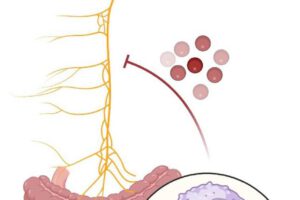

Investigadores descubren que el deterioro cognitivo está relacionado con la salud intestinal y la conexión entre intestino y cerebro